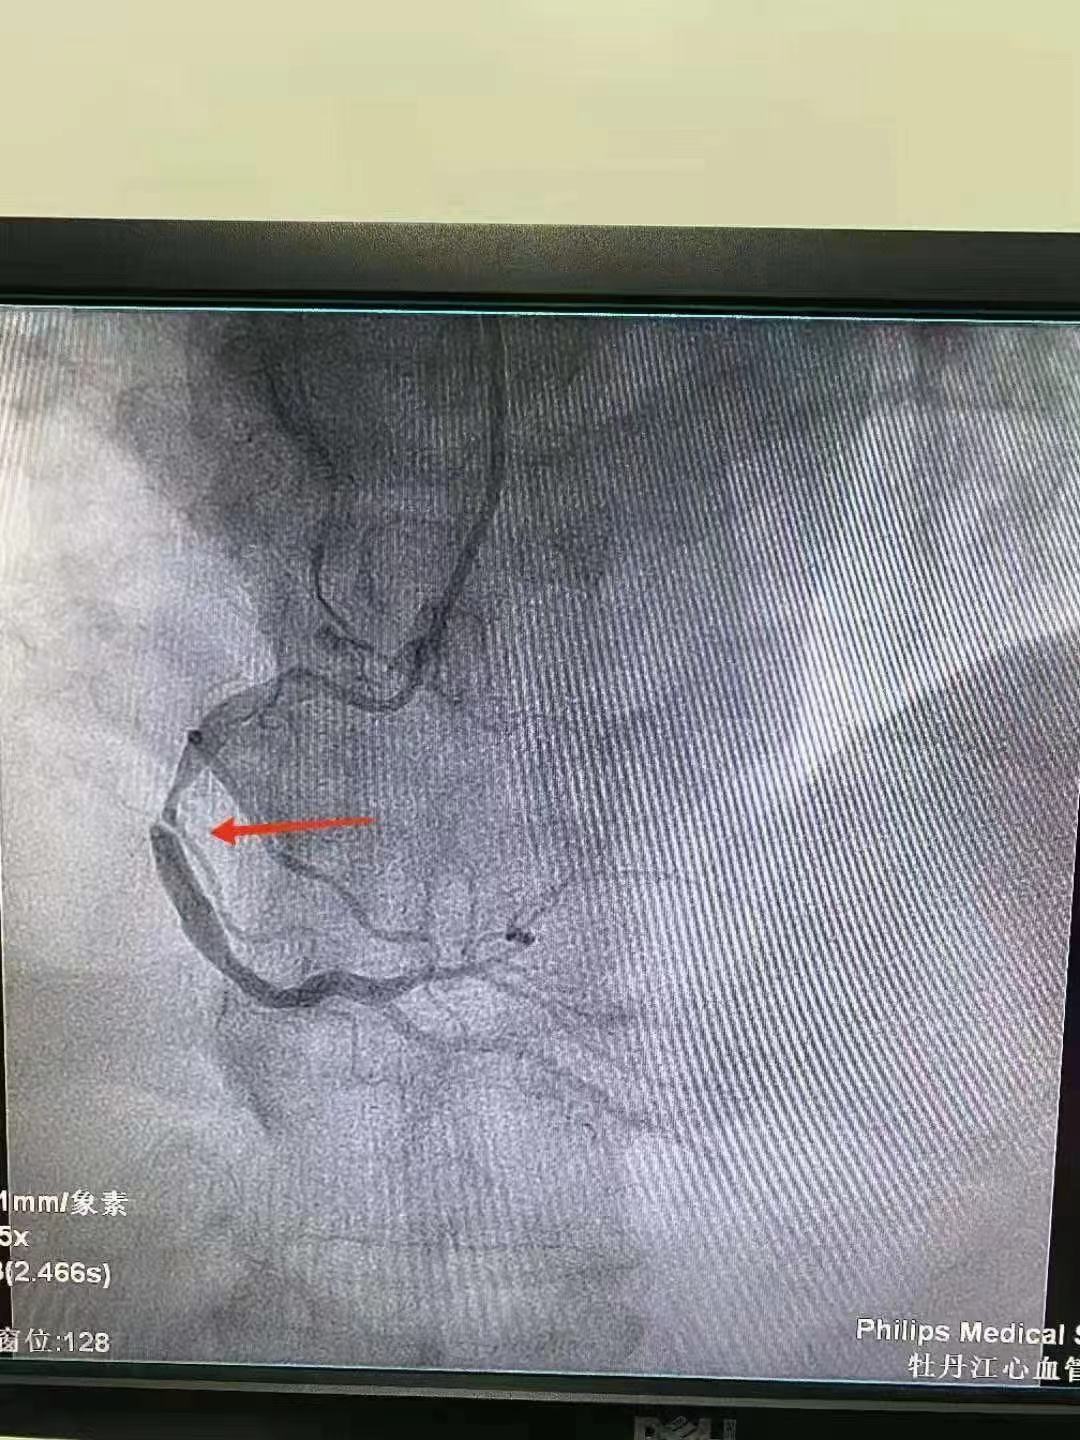

祝賀 牡丹江心血管病醫院關春普 主任團隊成功為患者植入Xinsorb生物可吸收支架!